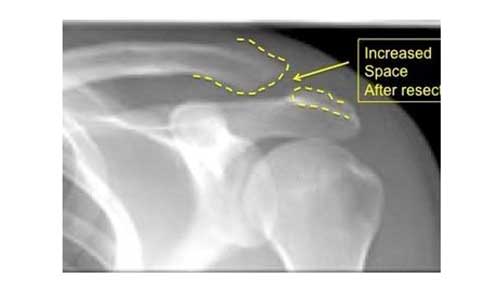

Με αυτή την επέμβαση αφαιρείται ένα τμήμα της κλείδας και του ακρωμίου μαζί με τον διάρθριο δίσκο, προκειμένου να δημιουργηθεί χώρος ώστε να μην υπάρχει κανένας ερεθισμός.

Η επέμβαση μπορεί να πραγματοποιηθεί αρθροσκοπικά ή ανοιχτά με τομή, δεδομένου ότι και οι δύο παρουσιάζουν την ίδια αποτελεσματικότητα.